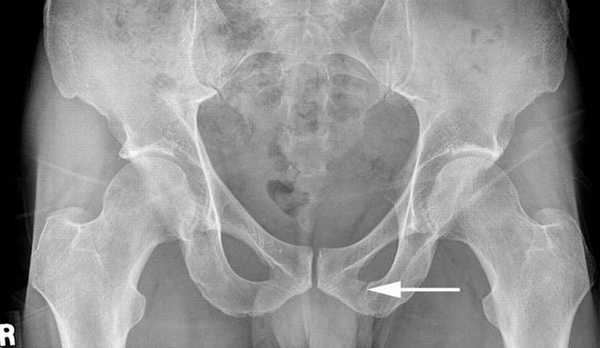

Перелом лонной кости